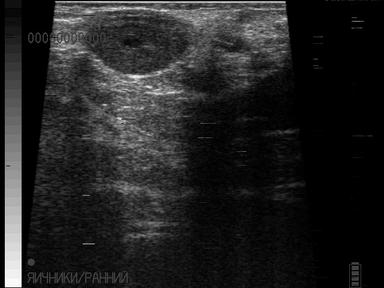

Первоначальное появление кист не проявляется расстройством полового цикла, болезнь часто диагностируется без клинических признаков. Ректальное исследование - наиболее распространенный и точный метод диагностики кист яичников, однако пальпацией отличить лютеиновую кисту от других видов кист достаточно сложно (киста желтого тела). Лютеиновая киста более плотная по консистенции, но это обобщенное показание. Более точной диагностикой является ректальное ультразвуковое исследование, которое дает возможность визуализировать структуры яичника, и различать лютеиновые кисты от других видов кист. При таких аномалиях необходимо своевременно начать лечение, чтобы не допустить экономические потери.